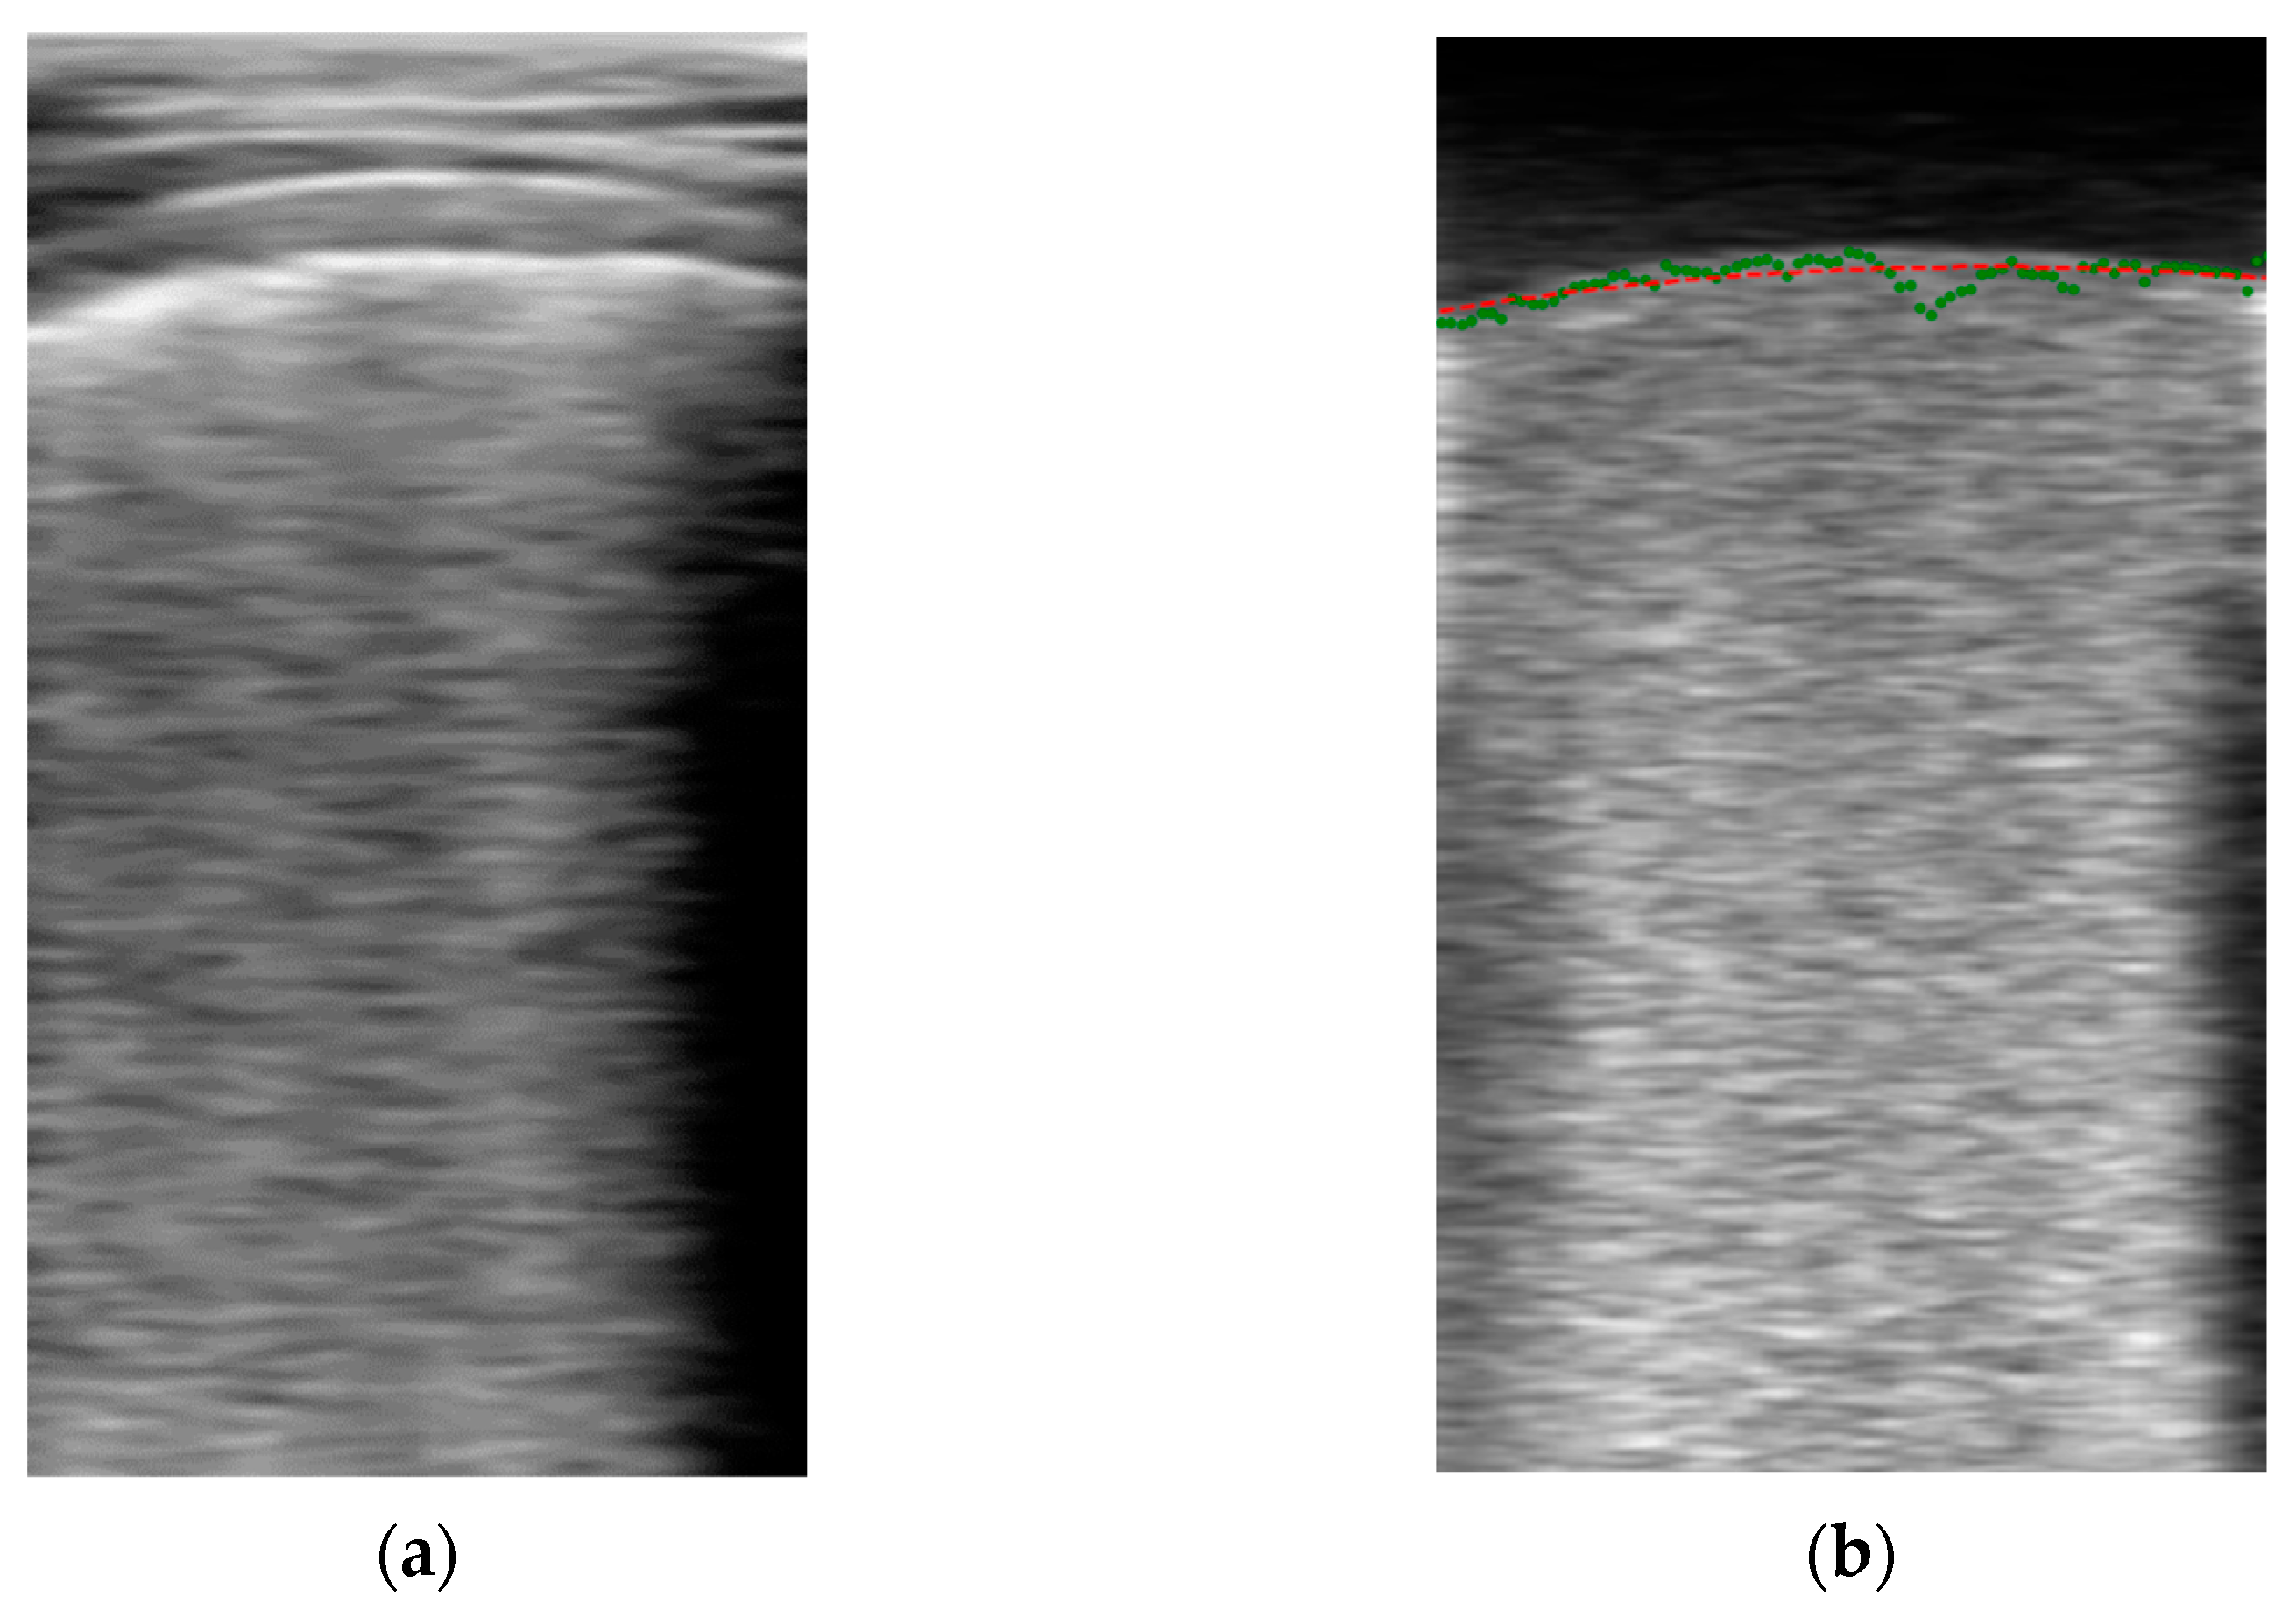

The algorithm for automatically segmenting the pleura is based on the fact that when the ultrasound probe remains stationary, the image above the pleura (fat and muscle) remains basically unchanged between frames, while variations in the image occur below the pleura due to the respiratory cycle. Then, by subtracting consecutive frames, an auxiliary image is formed, where the upper region is almost black and the lower part is bright. Furthermore, if several of these images are averaged, the random nature of the speckle in the lower part generates a quite homogeneous region that can be more easily distinguished from the upper region. The frontier between these regions can be considered a first approximation of the pleura line.

with L being the length of the averaging filter. Figure 4 shows an example output of the algorithm. On the left is the original Bi image of a frame, and on the right is its filtered version Vi, showing the two formerly mentioned dark and bright zones. For detecting their boundary, a dynamic threshold was applied to each vertical line of the filtered image, calculated from the average amplitude of the upper part of the image:

where is the vertical line of the filtered image at column j, is the vertical index to the pleura guess for that line, and thj the applied threshold. Figure 4b shows, with green dots, an example of this set of initial pleura raw guess points , which are then used to fit a second order polynomial to obtain a smooth representation of the initial guess (red line in Figure 4b).

Figure 4.

First pleura approximation example. (a) original B-scan image; (b) filtered image.

It is worth mentioning that directly applying a threshold to the original image (Figure 4a) is very prone to misdetections, as other horizontal bright lines in the upper region of the image are present, with pixel intensity values even larger than those of the pleura. On the other hand, the auxiliary image filtered by the proposed method is very suitable for a simple threshold detection because of its stepped nature.